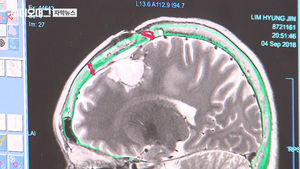

뇌암 치료 길 여는 '장벽' 자물쇠 풀렸다…임상시험 진행 자막뉴스 2019년 2월 17일 재생수3,944